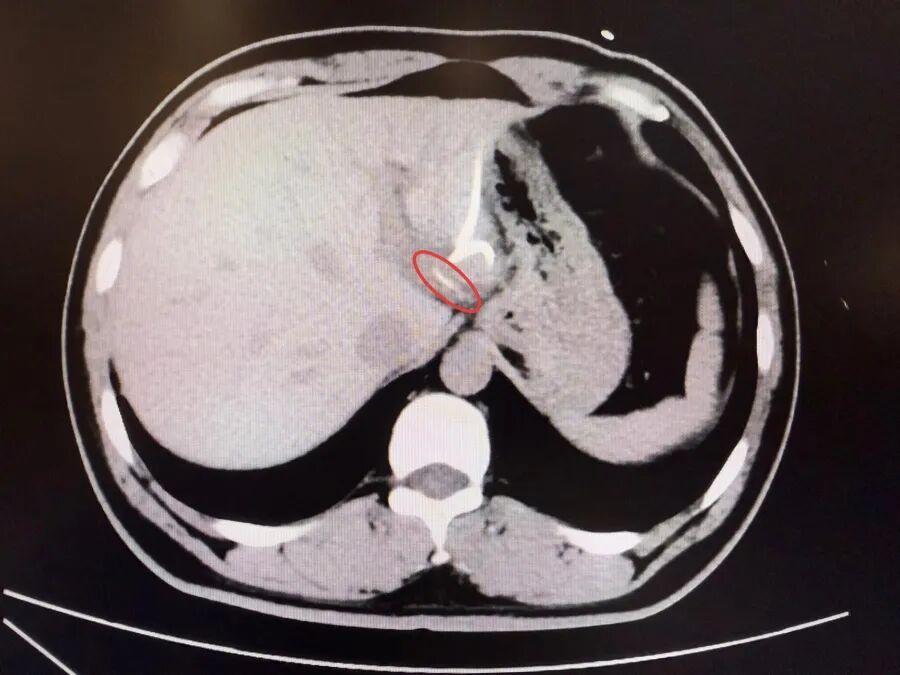

半月前,37歲的李先生(化名)誤吞魚刺卻未察覺,數天後出現腹痛、高熱(達40℃)等症狀,當地醫院診斷爲“肝膿腫”,治療後症狀反覆,CT檢查才發現肝臟左葉有魚刺——其已穿透胃壁入肝引發感染,十分危險,當地醫生評估後認爲,要徹底清除異物,需要進行左半肝切除手術,這讓李先生難以接受。

爲尋求更精準、微創的治療,李先生轉至復旦大學附屬中山醫院內鏡中心。“魚刺位置非常兇險,就在賁門旁刺入左肝,緊貼大血管。”接診的周平紅主任指出,魚刺位於賁門旁左肝處,緊貼大血管,且腹腔感染粘連嚴重,手術難度極高。